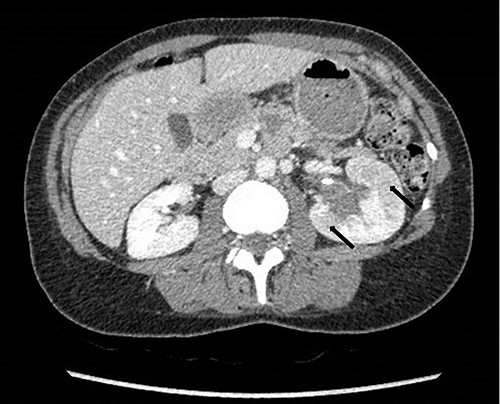

To investigate the bleeding source, she subsequently had a CT renal angiogram 3 days later that showed a narrow angle between origin of SMA and the aorta (Fig. 3) with multifocal areas of hypoattenuation throughout the left renal cortex (Fig. 4). It showed a compression ratio of 3.25 (diameter of pre-compressed vein =6.5 mm; diameter of compressed vein =2 mm) (Fig. 5).

Computed tomography angiogram on presentation showing pre-compressed LRV (right arrow); and compressed LRV (left arrow).